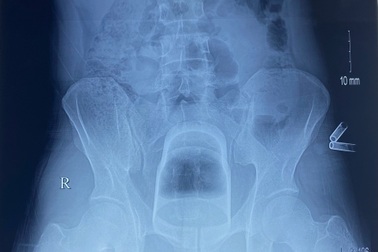

Nam thanh niên tự nhét cốc vào hậu môn, kẹt sâu phải mổ cấp cứuNgày 19/4, Bệnh viện Việt Đức cho biết, mới đây tiếp nhận ca cấp cứu, nam bệnh nhân 32 tuổi bị kẹt dị vật 12cm trong ống trực tràng.